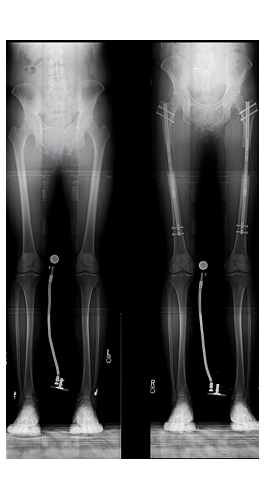

Dr. Wallace uses a minimally invasive technique to prepare the bone and place the lengthening rod. The device is implanted in the inner part of the bone and is controlled by a wireless remote to gradually lengthen the bone. The whole process takes about 1 hour. In most cases, there is an inpatient hospital stay.

Most often, patients elect to undergo femur lengthening only. Once the height is realized, the lengthening process is complete, and the newly formed bone begins to harden. Patients can then resume normal activities. Depending on how much length is desired, the limb lengthening process can take 3 months to 1 year.

Femoral Lengthening

Tibial Lengthening

For limb lengthening procedures, Dr. Wallace performs surgery using minimally invasive techniques with state-of-the-art internal lengthening devices. Dr. Wallace and his team are able to assist patients to reach their desired height, improve self-esteem, and maximize their physical capabilities. Through innovative implants and advanced surgical techniques, our goal is to help patients reach their top physical ambitions.

Stature lengthening surgery is personalized to help you reach your height goals. While every treatment is individualized, a typical femur lengthening is 8cm (3.1 inches), and tibial lengthening is 5cm (2 inches). In most situations, lengthening is performed on both femurs simultaneously. If additional height is desired, tibial lengthening can be done after complete femoral healing Summit Orthopaedics.

With the latest technology, bone lengthening works through a process called “distraction osteogenesis.” Though this technique, you grow your own bone. With each lengthening session, your body fills in the gap with new bone—in the same way you heal a fracture. This new bone is 100% your own bone, meaning it is identical in structure and composition.

With the latest technology, limb lengthening has been simplified. The lengthening rod is entirely inside the bone, so no wires or pins are outside the skin. Consistent physical therapy prevents some of the temporary side effects during lengthening such as joint stiffness and nerve stretching.